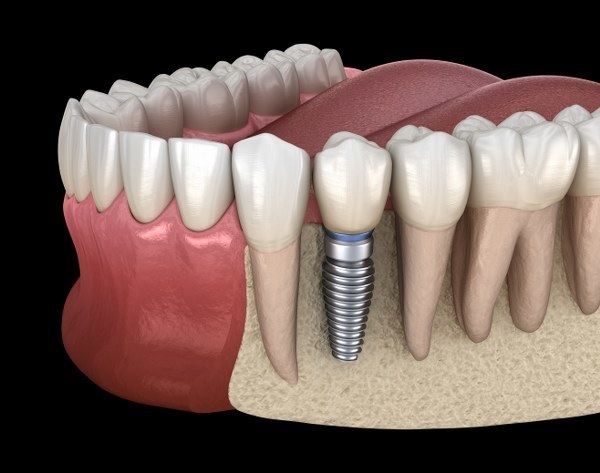

在進行手術前,醫生需要充分的瞭解患者的口腔情況,包括牙槽骨的狀況,因此患者需要進行CT檢查。所以一家口腔醫院要進行種植牙手術,擁有CT等數位化的影像設備是比較重要的。

由於不同患者的缺牙情況不同,所以種牙時所需的種植體型號和功能是不同的,所以所選種植牙醫院應擁有豐富的種植牙系統,不同種植牙系統其適應症不同,這樣可滿足不同患者的種牙需求。